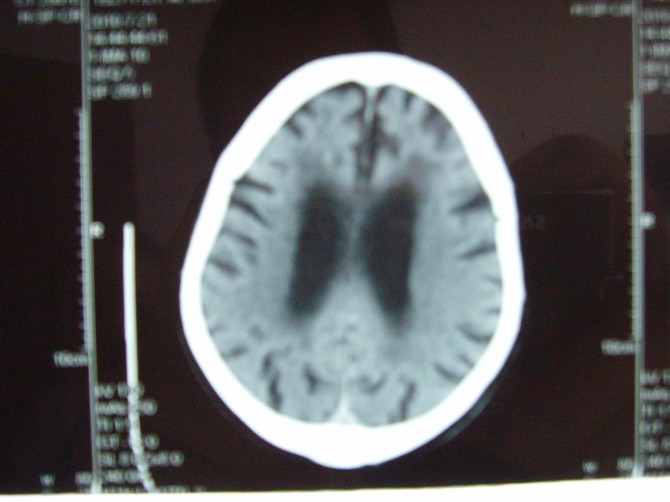

标题: CT27993:男 83岁 头晕伴双下肢无力一天 [打印本页]

标题: CT27993:男 83岁 头晕伴双下肢无力一天

脑萎缩。伴小脑齿状核、苍白球钙化.脑白质脱髓鞘病变

脑白质变性、脑萎缩。甲状旁腺功能减退。

1)双侧小脑半球脑软化灶。2)全脑萎缩。3)脑白质病。